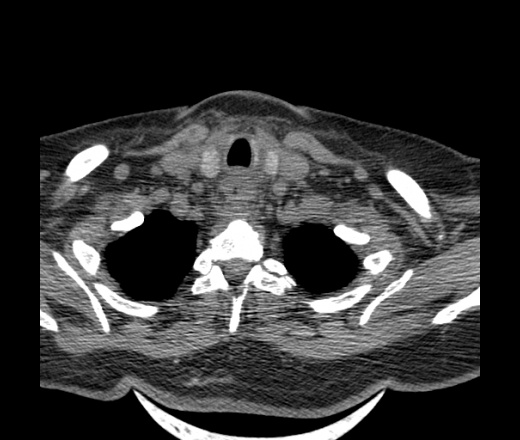

Женщина поступила в х/о спустя 4 дня после того как при употреблении карася подавилась костью.

Наличие газа в средостении на протяжении тел С2-С6 (медиастинальна эмфизема); рыбная кость на уровне тела С6.

При всем уважении, но говорить о медиастинальной эмфиземе, оценивая мягкие ткани шеи, как-то слишком резко. На мой взгляд, это ретрофарингеальное пространство.

Эвакуировали почти 100мл гноя. Но кость не смогли найти. Думаю что она даст дальнейшее ослоднение. Эндоскопически за черпалонадгортаной звязкой не смогли зайти в пищевод, все мягкие ткани отечные, просвет пищевода сдавлен. По всей видимости параэзофагеальная клетчака тоже задействована. Эмпиема, если ее можно так назвать, незнаю как правильно дошла до уровня яремной вырезки. Чем закончиться напишу. Ждем медиастинита.

Флегмона заглоточного пространства шеи, только операция, флегмоны вскрывают. Риск медиастинита.

Согласен с Вами; конечно, наличие газа в клетчатке ретрофарингеального пространства (затмение с опечаткой..). К сожалению, процесс "продвигается" к медиастиниту. Но почему никто, не отмечает наличие рыб. кости; или это для Всех очевидно?

Так вы уже отметили. Хотя ориентировал бы не скелетотопически, а на перстнечерпаловидный сустав.

Кость то мы сразу выявили, размеры где то 17*2мм, но ее так и не получается найти в этой каше